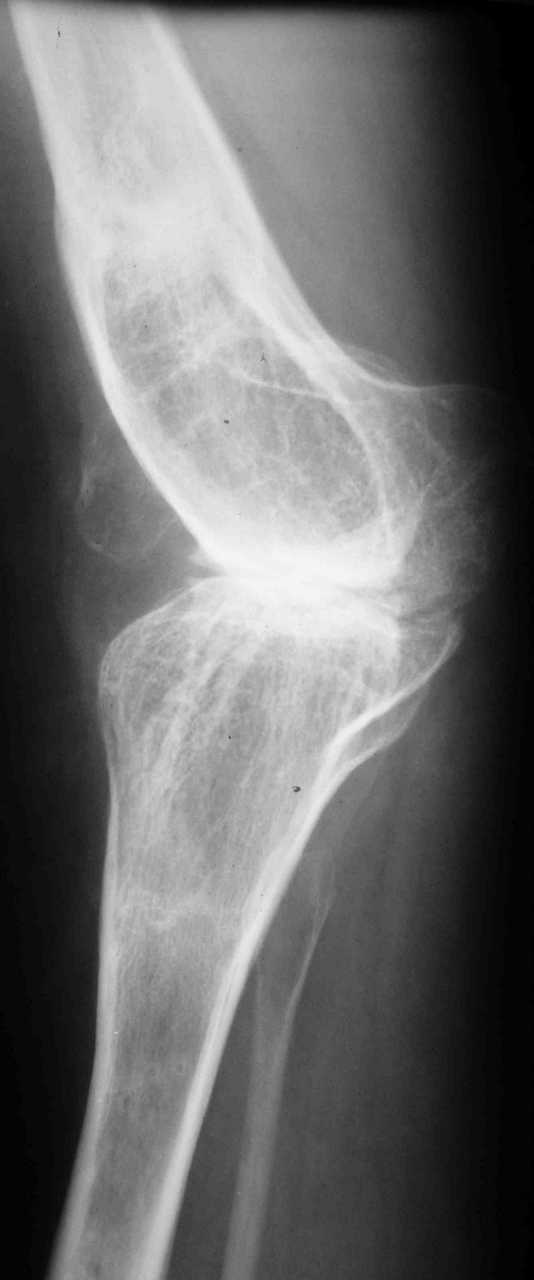

Re: эндопротезирование коленного сустава

В настоящее время нет возможности сделать осевые снимки всей конечности. Это всё чем я раполагаю на сегодняшний день.

Пациентку беспокоит только выраженный болевой синдром в коленном суставе.